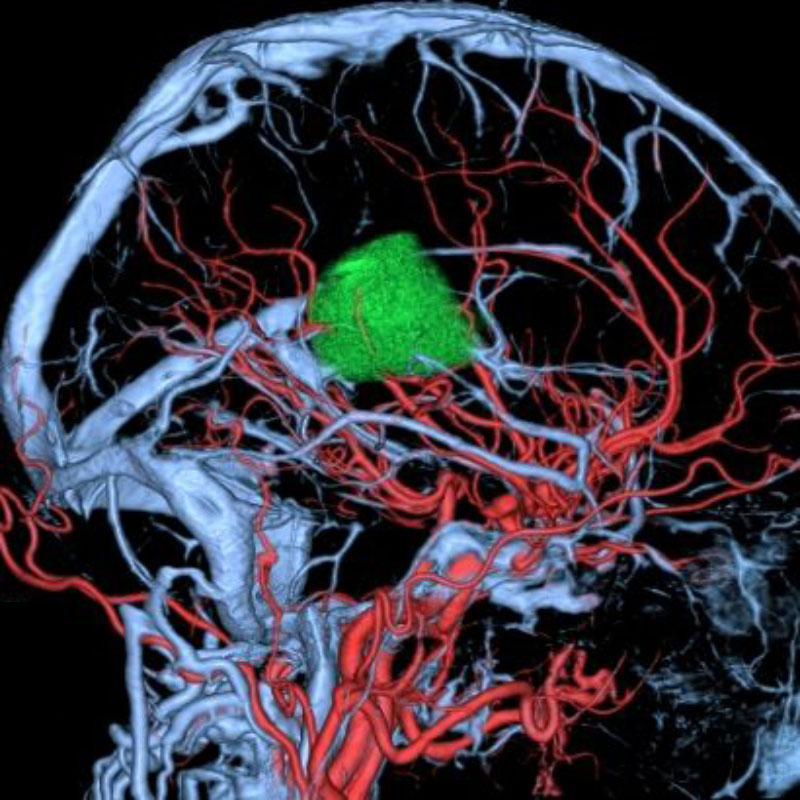

脳動静脈奇形

血管塞栓術

松田/濵田/元永